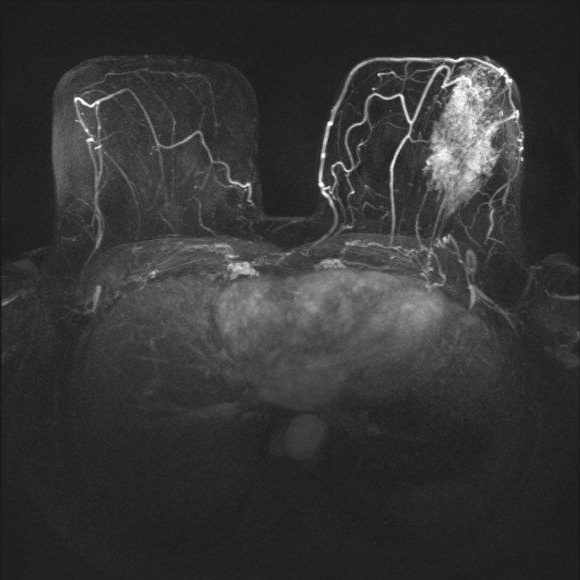

Mamma-MRT: Brusttumor Mamma-MRT: Brusttumor

Mamma-MRT: Brusttumor

(Zum Vergrößern bitte anklicken)